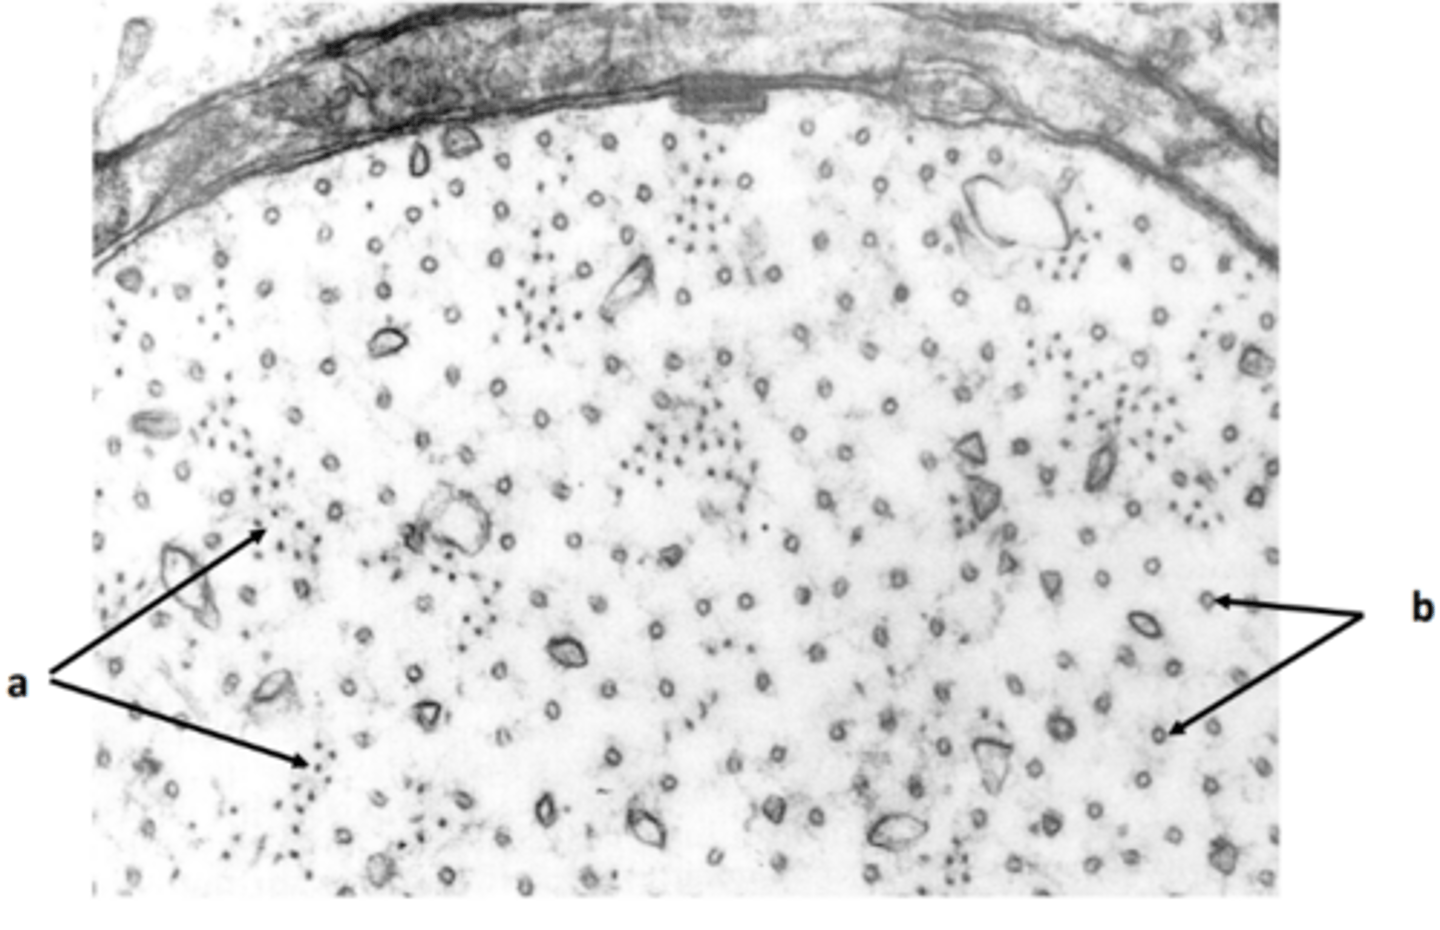

extrafusal myofibers

a: specific tissue type

<p>a: specific tissue type</p>

2

New cards

intrafusal muscle fiber

b: specific tissue type

<p>b: specific tissue type</p>

3

intrafusal muscle fiber (muscle spindle)

c: specific tissue type

<p>c: specific tissue type</p>